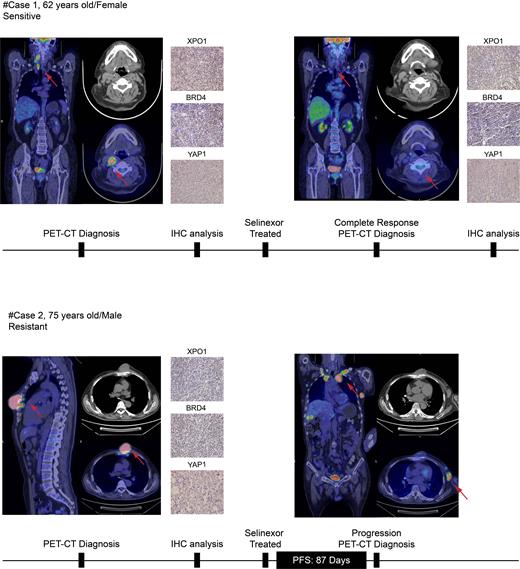

BRD4, BRD7, ZMYND8, and YTHDC1 were identified as top Selinexor resistance candidate targets through CRISPR/Cas9 Screen. The knock-down of BRD4 enhanced the killing ability of Selinexor in vitro and reduced tumor burden in subcutaneously transplanted tumor mice after treatment with Selinexor in vivo in DLBCL. The combined treatment with BRD4 inhibitor JQ1 and Selinexor had a stronger ability to promote cell apoptosis, enhance DNA damage and reduce nascent DNA compared with the single drug group. Hematological and organ toxicity tests confirmed an acceptable toxicity for the combined drug regimen. ChIP-seq differential peaks and RNA-seq differential genes analysis elucidated the crucial role of YAP1's sub-cellular localization under Selinexor treatment. YAP1 nuclear translocation enhanced transcription and formed an interaction with BRD4, resulting in augmented BRD4 binding domain, and finally lead to the resistance of Selinexor. PET/CT imaging showed that one patient with high XPO1 expression achieved complete response (CR), exhibiting a sensitivity to Selinexor treatment, but the other exhibits resistance associated with a lack of XPO1 expression and BRD4-regulated acetylation.